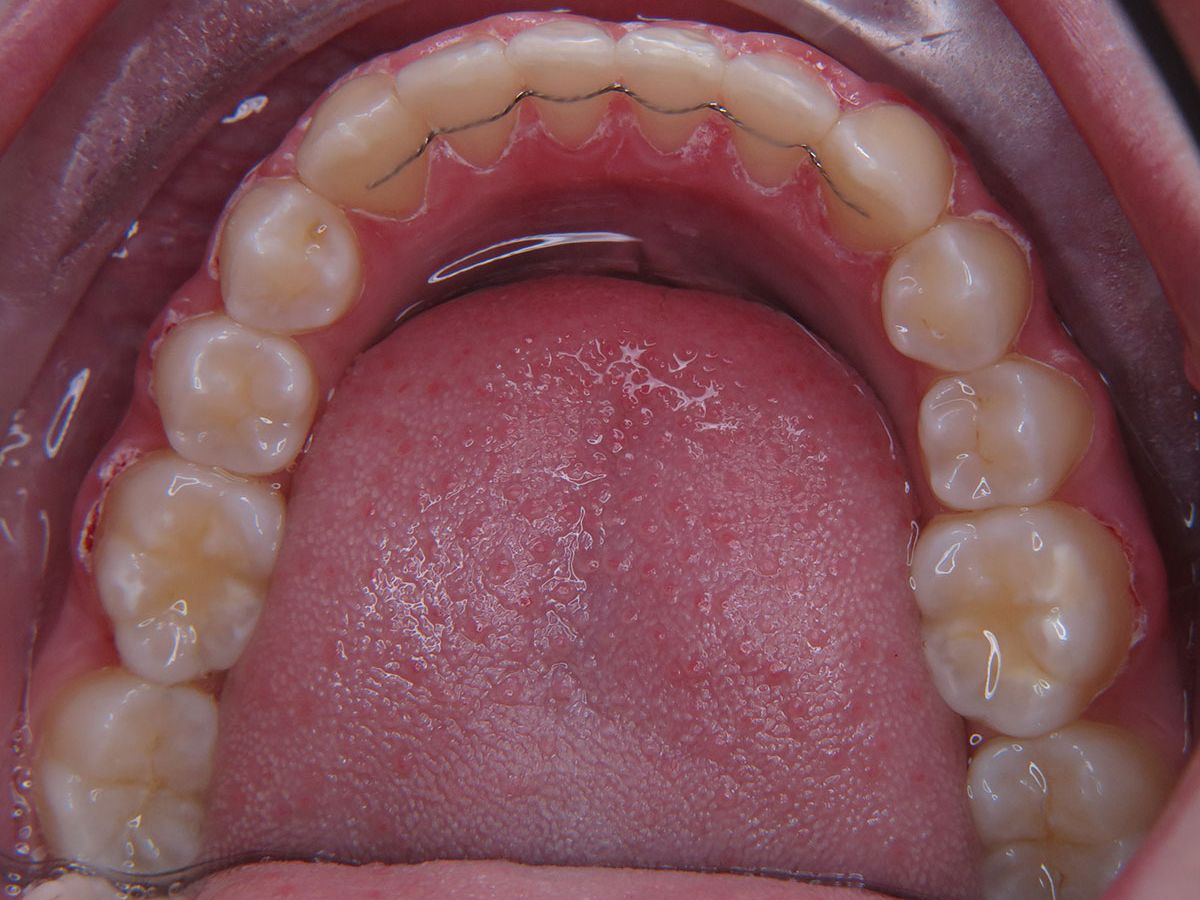

Um das Ergebnis dauerhaft zu sichern, einem Rückfall vorzubeugen und auch weiteren unerwünschten Zahnbewegungen entgegenzuwirken, kommen Stabilisierungsgeräte zur Anwendung. Diese gibt es als herausnehmbare Nachtspangen (Platten oder transparente Schienen) und in Form festsitzender Drähte, sogenannte „Retainer", die auf die Innenseite der Frontzähne geklebt werden.

Die Langzeitstabilisierung mit einem Retainer bietet den zuverlässigsten Schutz vor Rückfällen und alterstypischen Veränderungen der Frontzahnstellung. Im Laufe der Tragezeit können jedoch die Klebeverbindung am Bogen oder der Draht selbst sich lösen oder brechen. Um den Behandlungserfolg nicht zu gefährden, sollte in einem solchen Fall eine sofortige Reparatur oder Erneuerung des Retainers erfolgen.